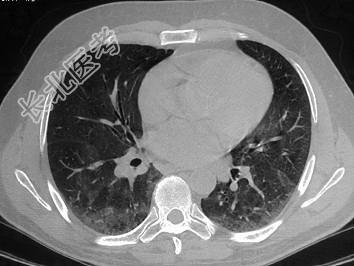

- 单项选择题患者因反复咳浓臭痰2年入院,胸部CT如图所示, 最有可能的诊断是 ( )

A、脓胸

B、肺结核

C、支气管扩张

D、肺癌

E、以上均不正确